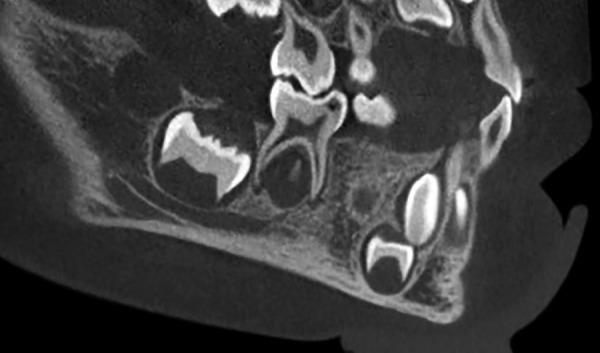

Hidden caries is a dentinal lesion beneath the dentinoenamel junction, visible on radiographs. A single report described this lesion in primary dentition. This case report describes a case of hidden caries in a mandibular second primary molar, misdiagnosed as malignant swelling. A 3-year-old white girl was referred to the Department of Pediatric Dentistry with a chief complaint of pain and extraoral swelling on the right side of the mandible for the last 3 months. She was earlier referred to the surgical department for biopsy of the lesion. Radiographic and computed tomography scan examination showed a periapical lesion with buccal plate resorption and radiolucency beneath the enamel on the mesial part of tooth 85. The tooth was extracted, and follow-up of 2 years showed normal development of tooth 45. The main problem is early detection and treatment, since the outer surface of enamel may appear intact on tactile examination.

隐匿性龋是位于牙本质釉质界下方的牙本质病变,在X线片上可见。有一份报告描述了乳牙列中的这种病变。本病例报告描述了一例下颌第二乳磨牙隐匿性龋被误诊为恶性肿胀的病例。一名3岁白人女孩因右侧下颌疼痛和口外肿胀3个月为主诉被转诊至儿童牙科。她之前被转诊至外科进行病变活检。X线片和计算机断层扫描检查显示85号牙近中部分根尖周病变伴颊侧板吸收以及釉质下方的透射区。该牙被拔除,2年的随访显示45号牙发育正常。主要问题是早期发现和治疗,因为在触诊检查时釉质外表面可能看起来完好无损。